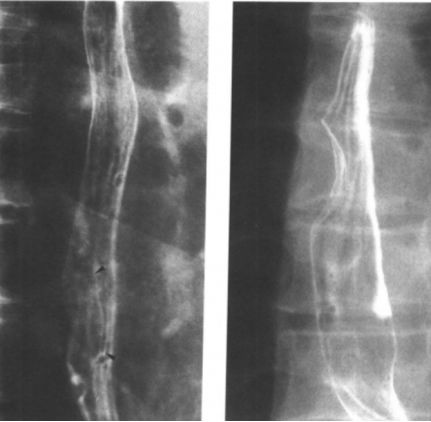

食管痉挛:螺旋状、波浪形。

食管痉挛:螺旋状、波浪状